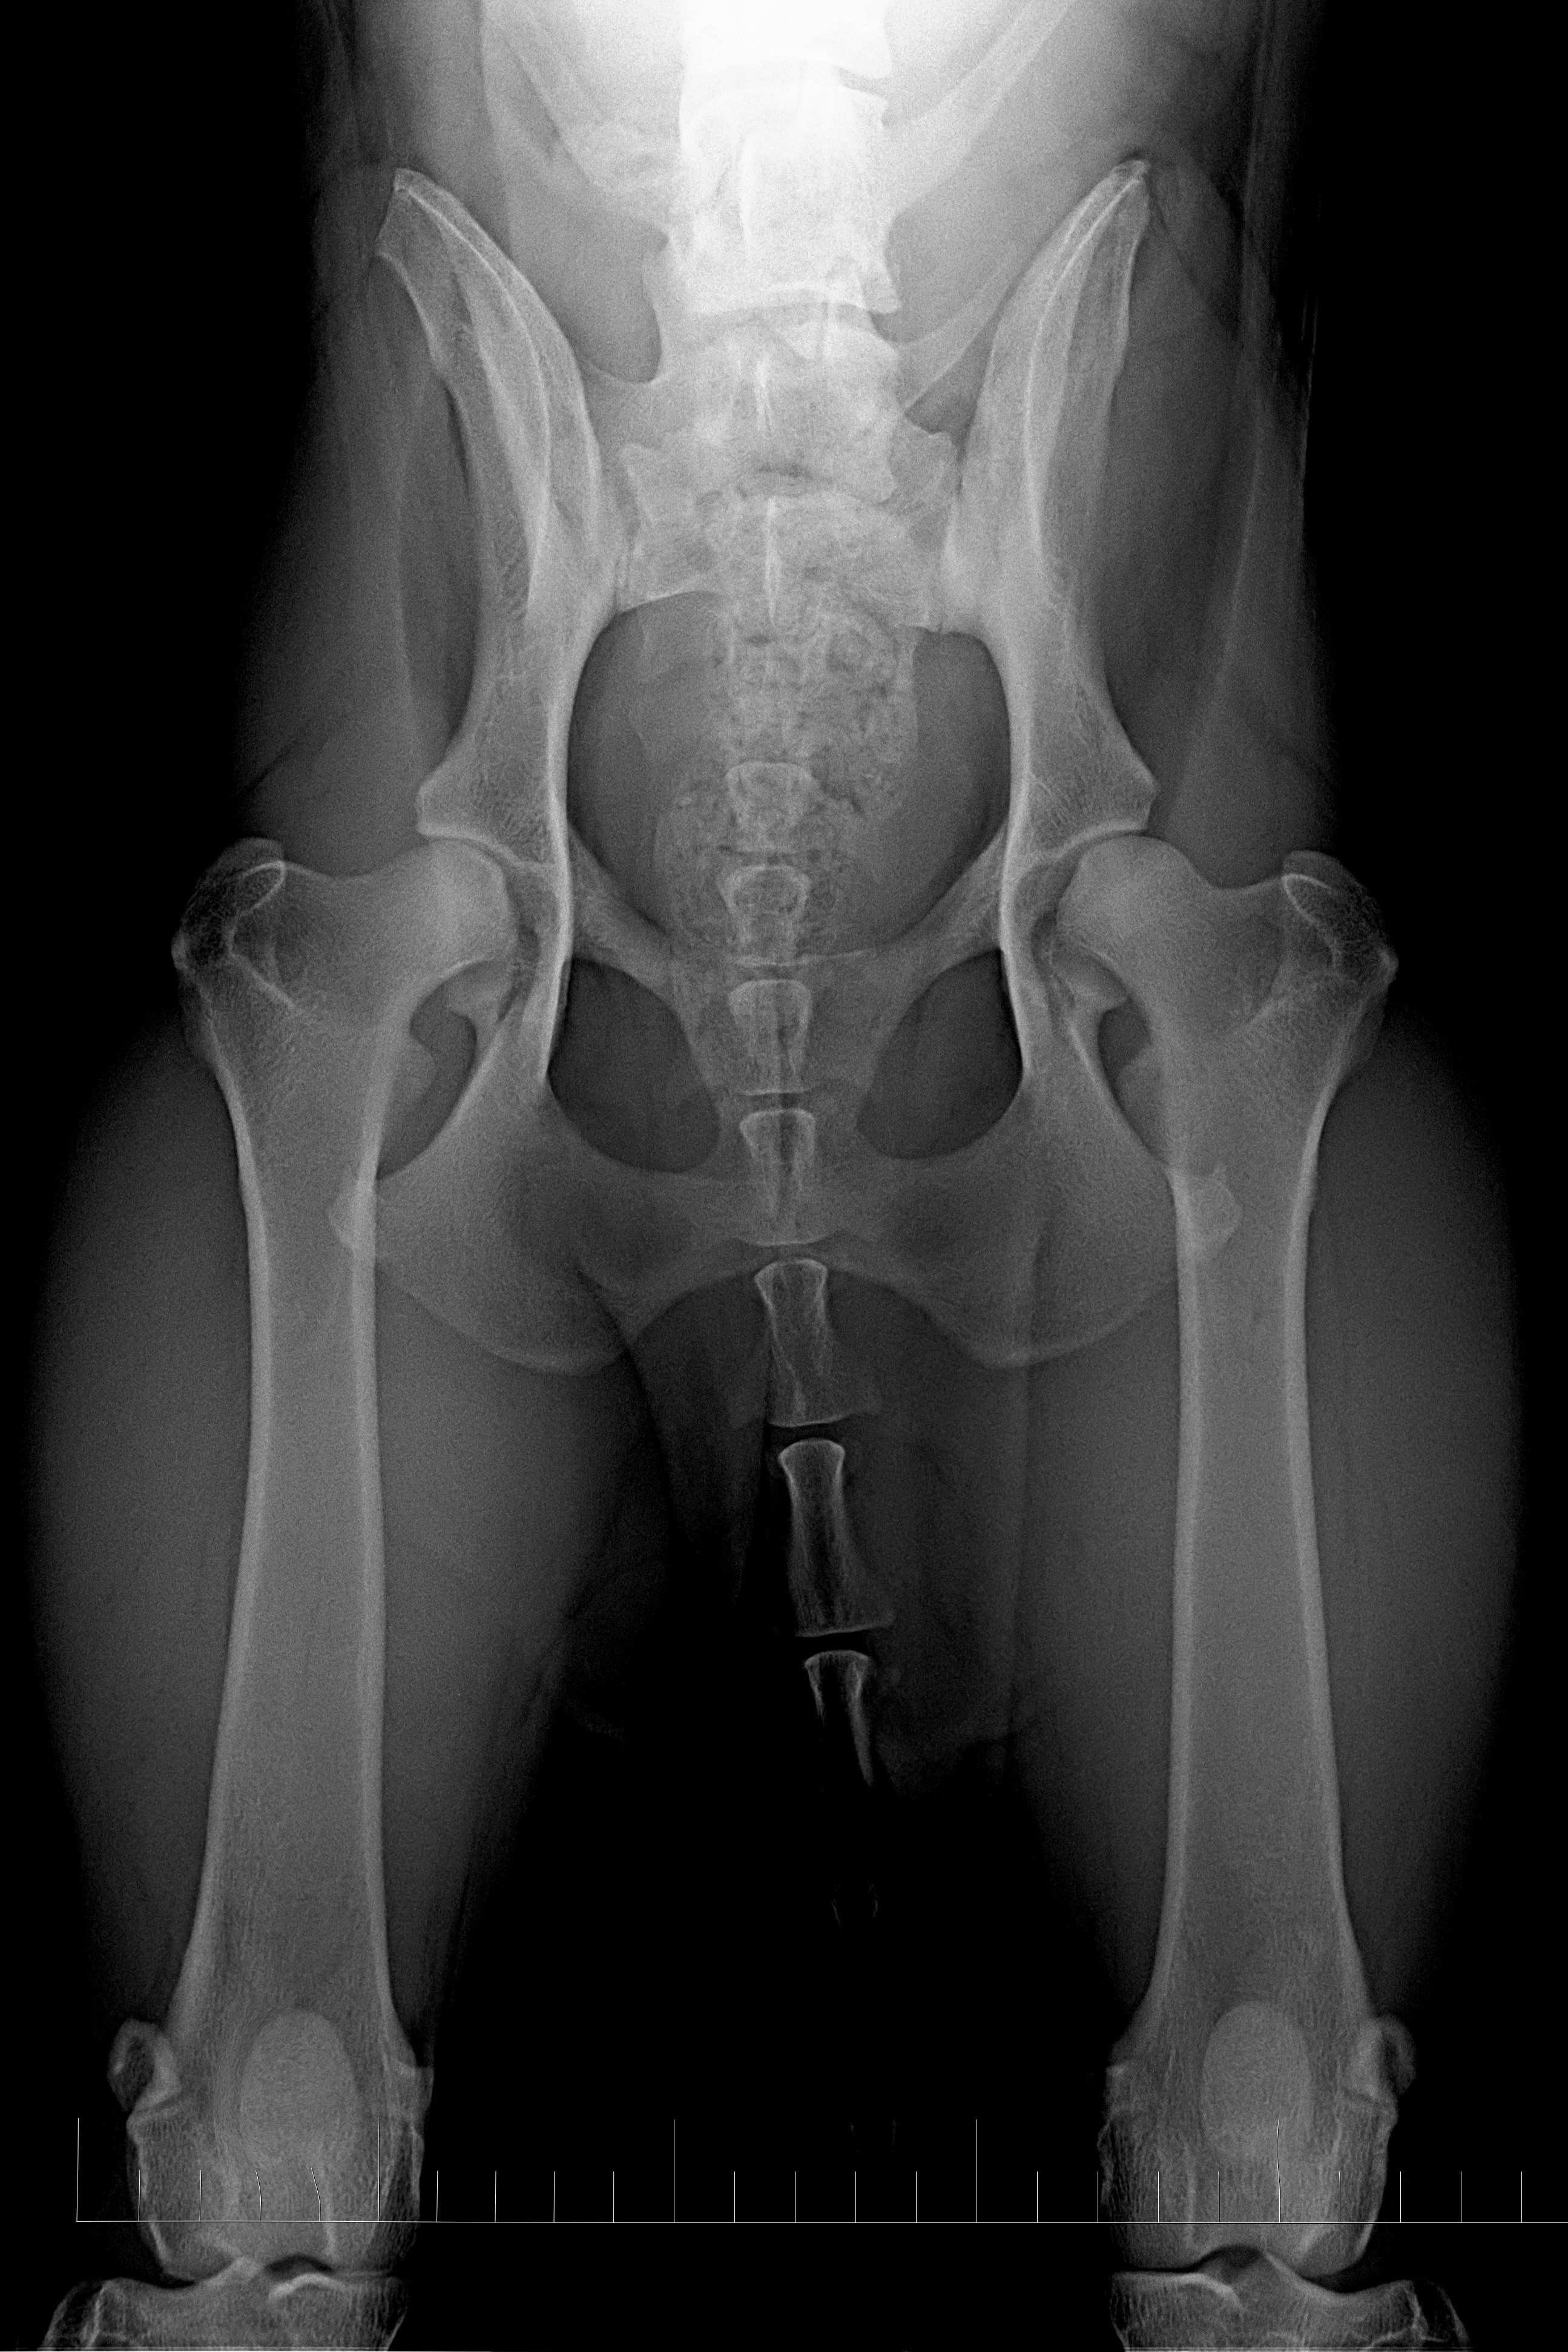

(3) 7 měsíců VD 1

(3) typ 3 po korekci polohy pánve